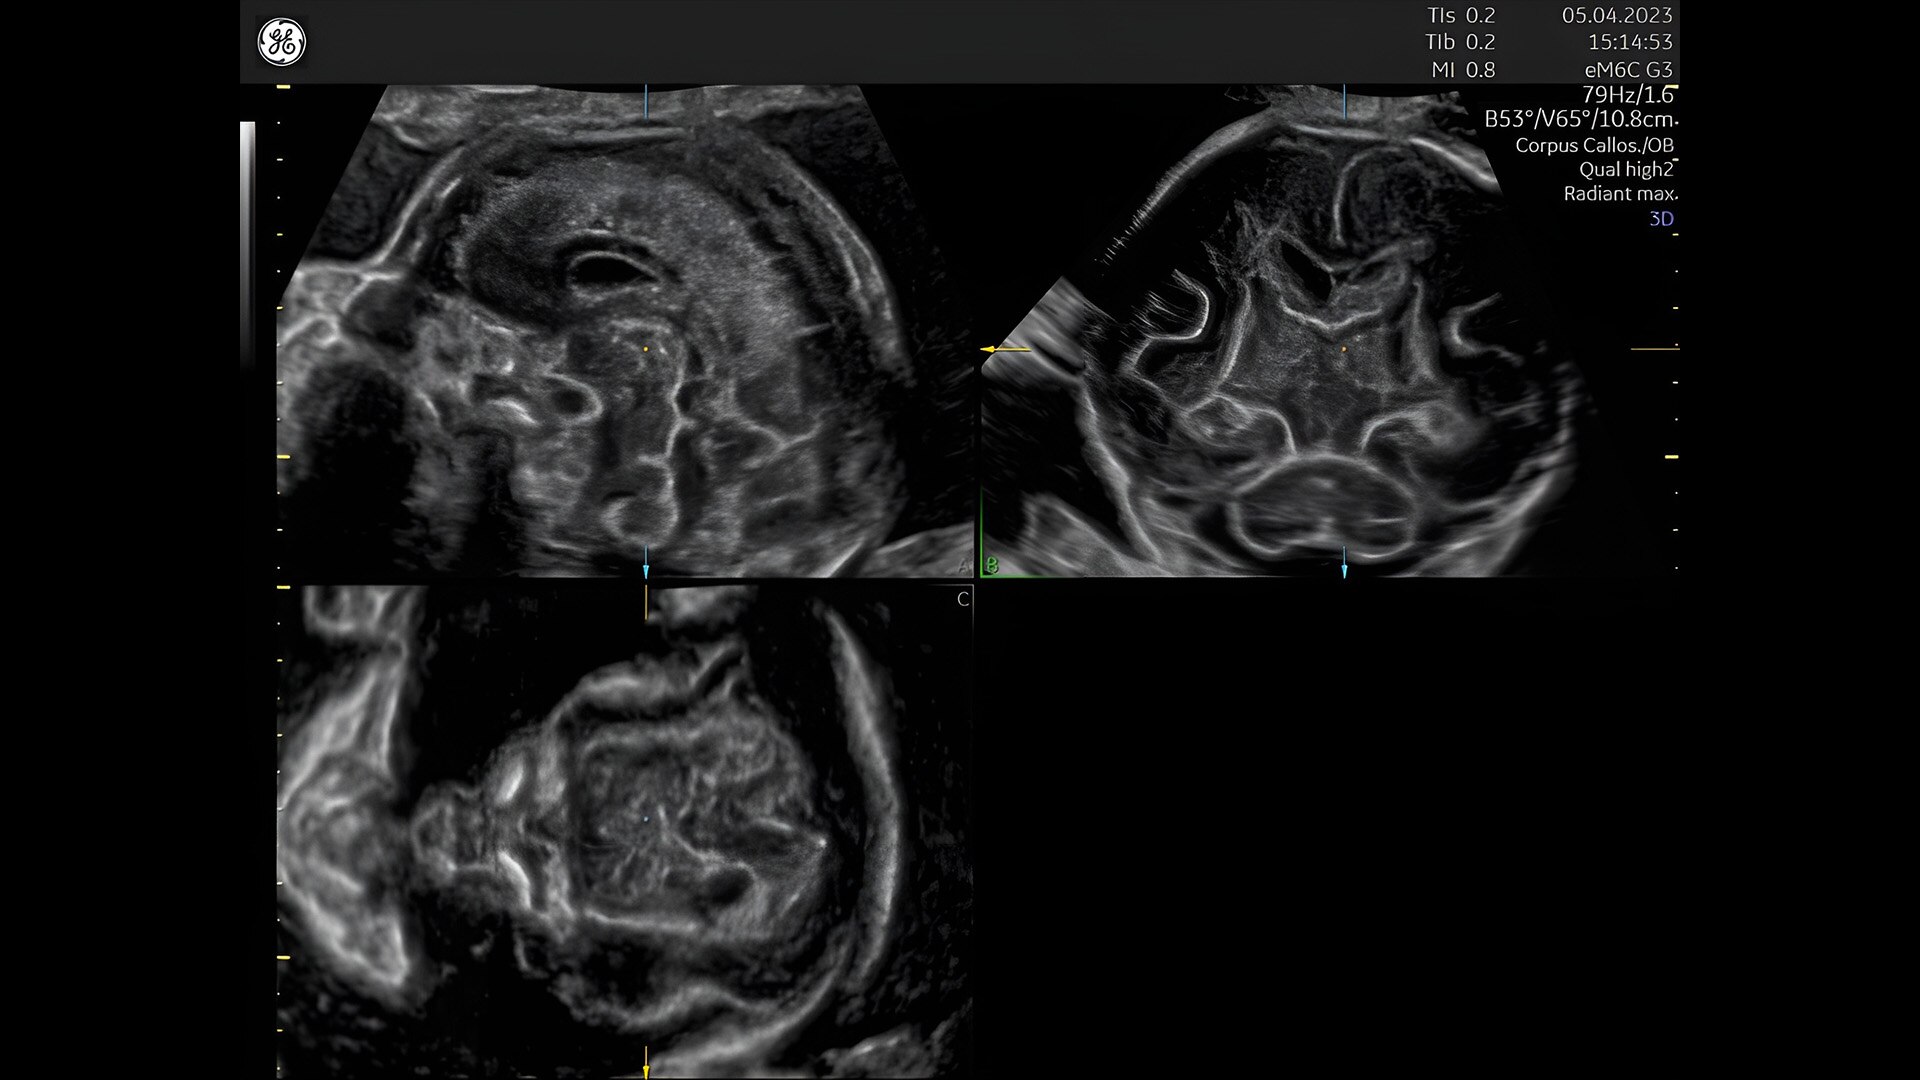

Fetal heart evaluation

Get to the heart of the matter

Identifying fetal cardiac abnormalities earlier means you can intervene sooner, plan for delivery, and potentially improve outcomes. The Voluson Expert 22 provides a full solution of progressive tools, to help distinguish the tiniest structures with stunning clarity to provide patient answers faster.